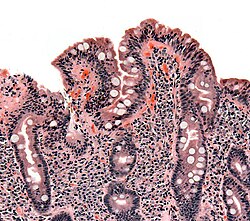

Biopsy of small bowel with coeliac disease

Coeliac disease is a chronic autoimmune disease mainly affecting the small intestine, caused by an abnormal immune system response to gluten. The disease's classic form can affect any age group, causing symptoms of malabsorption. Non-classic coeliac disease is more common in adults, characterised by vague abdominal symptoms and complications in organs outside the gastrointestinal tract. To those with a genetic predisposition to the condition, eating gluten causes inflammation in the small intestine, damaging its lining and leading to malabsorption. Diagnosis is based on symptoms, blood tests, and biopsies of the small intestine. It is treated by implementing a gluten-free diet; symptoms can improve within days. Diagnoses have increased due to increased awareness and availability of blood testing, but it is still thought to be underdiagnosed. Most people develop the disease before the age of 10; it is slightly more common in women than in men. (Full article...)